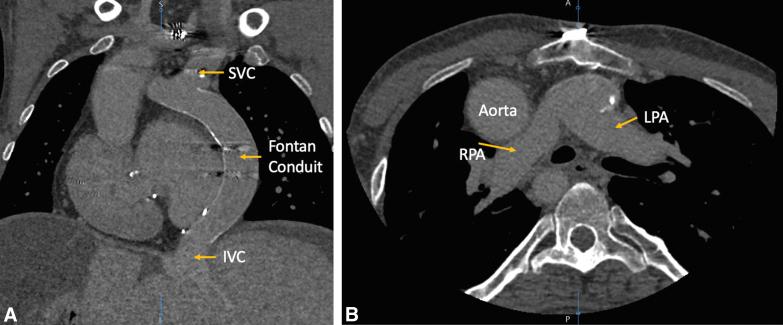

Combined heart and liver transplant in a patient with failing Fontan and total situs inversus.

Combined heart and liver transplant in a patient with failing Fontan and total situs inversus.为一名功能性单心室(Fontan)循环衰竭且完全性内脏反位患者实施心脏联合肝脏移植手术。